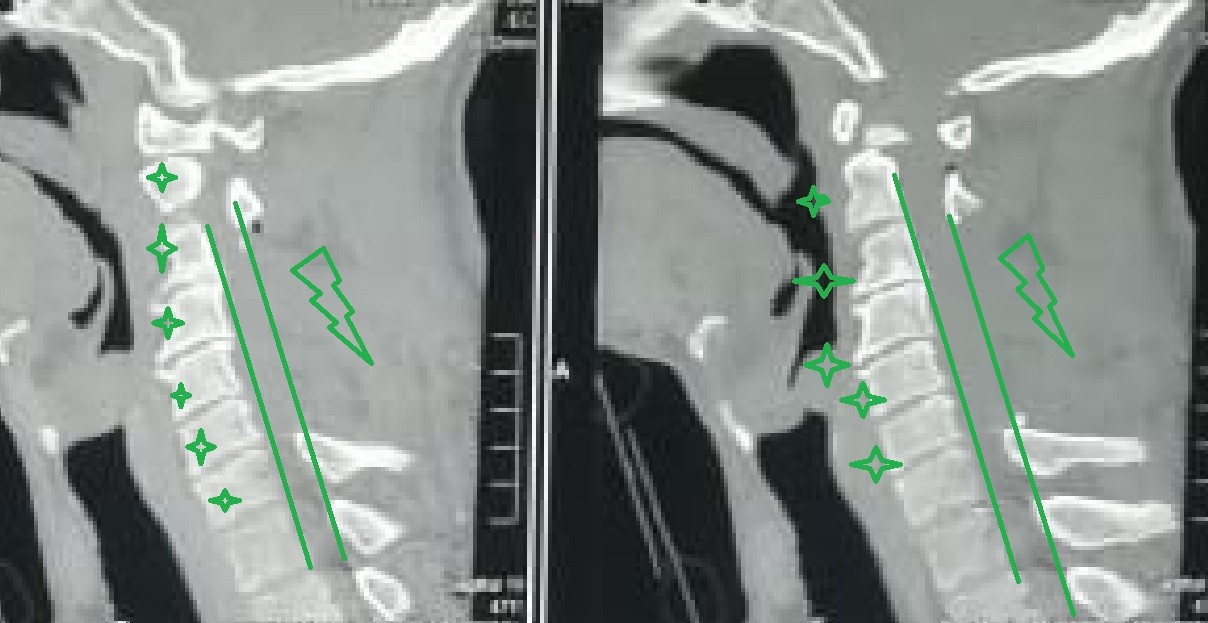

A successful surgery was performed to decompress a narrowed cervical spinal canal. This condition occurs when the spinal canal in the neck area narrows, causing pressure on the spinal cord and nerves supplying the arms and hands.

• Accurate preoperative planning using advanced imaging